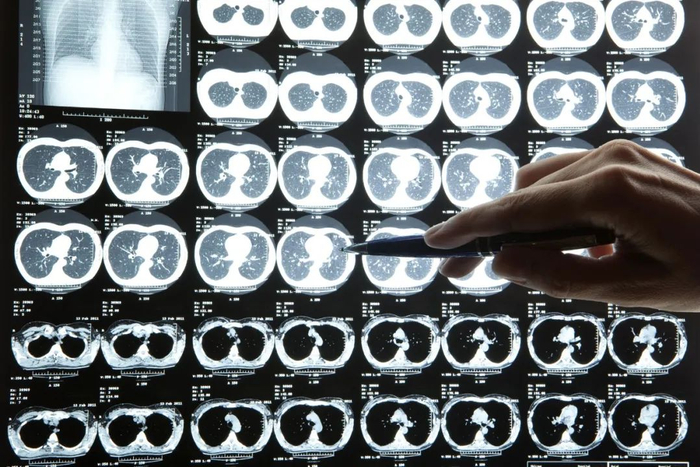

医生肉眼阅片要5-15分钟,

我们的AI只要2秒

魏东 腾讯天衍实验室 研究员

投入使用后,医护人员给的反馈都非常理想,因为阅片不用那么累了。当时医生阅读、分析CT影像的压力非常大,临床诊断标准改变以后,每日新增确诊病例暴涨将近十倍,每位患者做一次胸部CT,会产生300张影像,每次医生肉眼阅片要耗费5-15分钟。

已经确诊的治疗期患者,每5天也要做一次CT检查,当时整个湖北省累计超过6万例确诊患者。

AI最快两秒钟就能判断出这个人是否得了肺炎,他得的肺炎是不是新冠肺炎。如果AI判断这个人是新冠肺炎,它还会在CT影像中标示出病灶,告诉医生它判断的依据,标示的过程最多需要一分钟。

AI的判断不能直接作为医疗诊断的依据,但是可以为医生提供参考,大大提高了诊断效率。

有些医生刚用的时候,担心AI的准确率。但根据我们的研究,我们的AI模型比低年资的医生诊断准确率高。而且随着病例数据越来越多,我们会不断训练、调整算法,让它的准确率不断上升。

在这次新冠肺炎疫情中,阿里达摩院研发的AI+CT影像诊断技术,平均识别不到 20 秒,准确率达 96%。

影领科技、推想科技、深睿医疗等公司,也都纷纷推出了针对新冠肺炎的CT影像AI筛查产品。武汉市中心医院使用了数坤科技的AI辅助诊断系统,能够快速读取胸片,2到3秒内识别炎性病灶,医院影像科主任王翔说,这一系统“为医生提升了50%的工作效率”。

事实上,AI医学影像,被公认是目前最成熟,也是最有可能率先实现商业化的医疗AI产品。几千份病例的数据,就可以开发出一套准确率相对较高的诊断产品。

疫情突然爆发,给一线的影像医生带来两个巨大的挑战:一是阅片量激增,大量都是高强度的重复性体力劳动,二是基层医院设备不足,医生经验和素质参差不齐。这两点都会导致误诊和漏诊。

按照疫情最严重时的状况,湖北省每天新增1万多名疑似患者,他们的CT片总计超过数百万张。与此同时,还有几万名确诊患者的复查需求,据估计,一线的阅片医生们每天的工作量达到500万张。

机器人分析X射线脑层析成像

AI可以解决医生们的燃眉之急。

中国工程院院士潘云鹤说,目前用于分析胸片的AI模型,对肺癌的检测率达到了98%以上,远远高于人工。